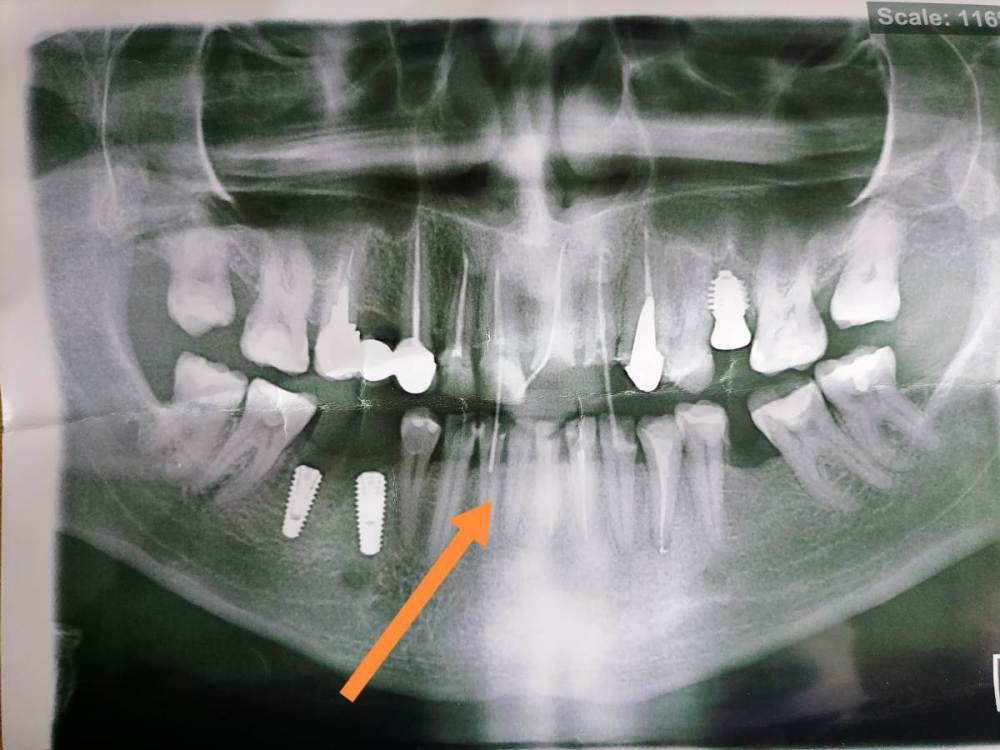

Добрый день, уважаемые доктора ответьте пожалуйста на вопрос. Врач обточил зубы под безметаловые коронки e. Max.

Два зуба депульпированных, а два живых.

И вот один из этих живых зубов, реагирует на нажатие, холод и горячее.

Сам по себе не болит.

На сколько это критично? Нужно ли удалять нерв?

Сейчас хожу с временными коронками, постоянные будут готовы к концу месяца, хотелось бы решить вопрос до установки постоянных коронок.

Врач говорит, что плохо если будет болеть самопроизвольно, ночью и т. Д. А так - нормально, потому что зуб живой. Хотелось бы услышать ваше мнение. Спасибо!

Ps. Палочка на снимке с верхнего зуба торчит :)